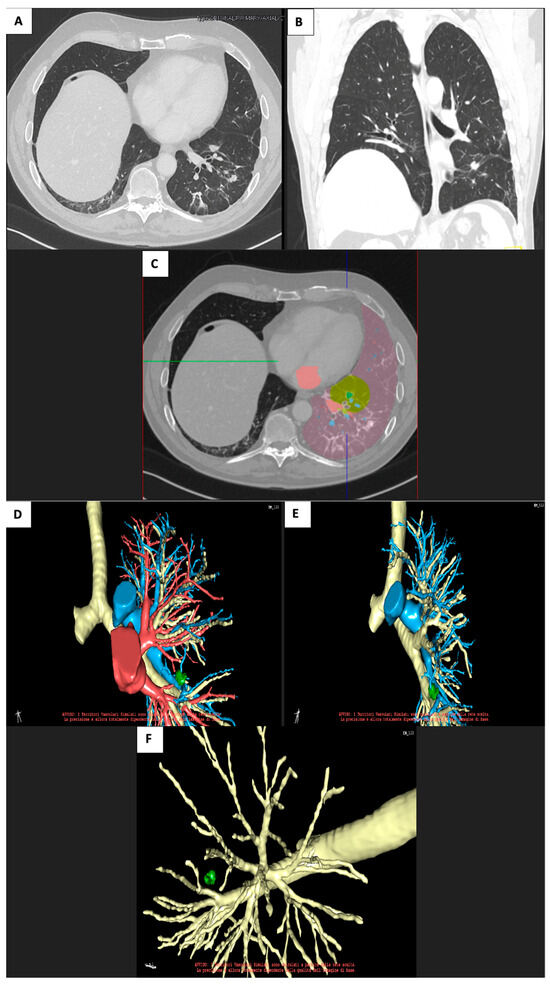

2.1. Case 1